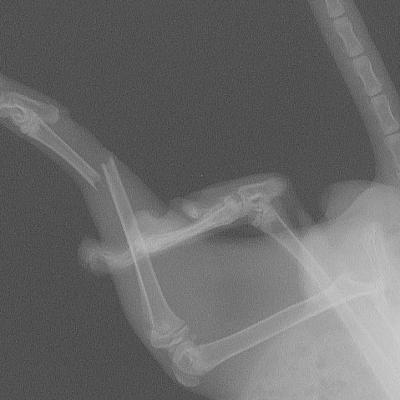

Fracture du tibias d'un lapin